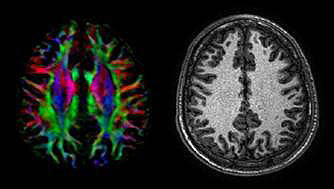

White thing tracts

The figure below shows the white thing tracts in a mature brain. Notice the colored areas that reveal the tracts from front to back of the brain, allowing for good advice both from front to back as well equally from right to left.

Mature brain